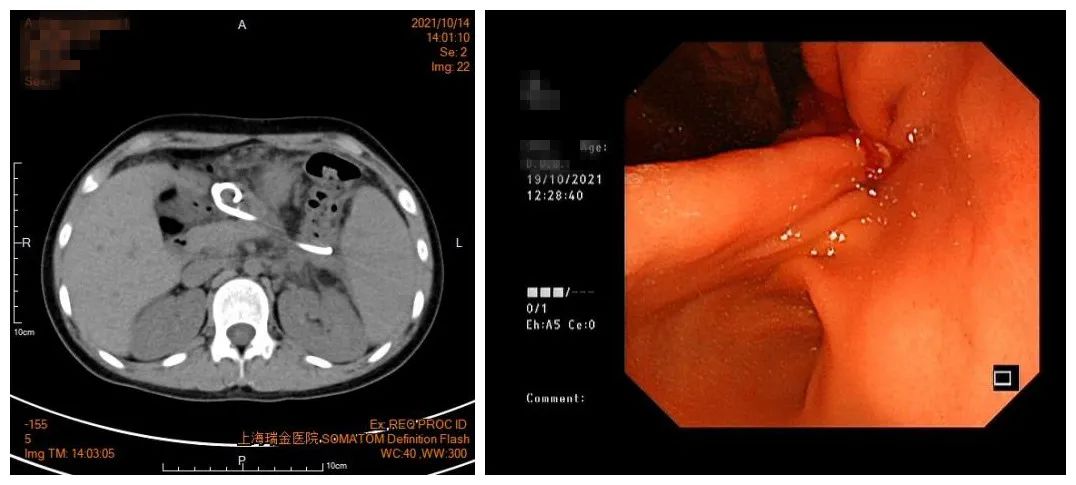

很快,小熙体温恢复正常,呕吐和腹痛缓解,也不再吵着拔管子了。1个月后复查影像学,小熙的囊肿也基本消失。出院前,医生将新增的鼻囊肿引流管剪断改为内引流,鼻子里没有管子的羁绊,自由多了,小熙特别高兴。

最后一次复查CT囊肿完全消失

胃里的也支架拔除了

目前,小熙已出院2个多月,再也没有出现发热,腹痛及呕吐,基本恢复了正常饮食。更重要的是,复查CT医生发现她的囊肿完全消失了,拔除了2根支架,胃壁的穿刺瘘口也很快愈合了,小熙完全康复了!不过这一次,小熙也懂得了健康饮食的重要性。